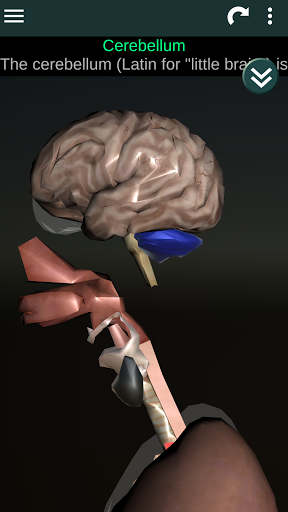

Menampilkan model anatomi 3D dari organ utama tubuh manusia dan penjelasannya masing-masing.

* Otak, yang meliputi otak, otak kecil, dan batang otak.